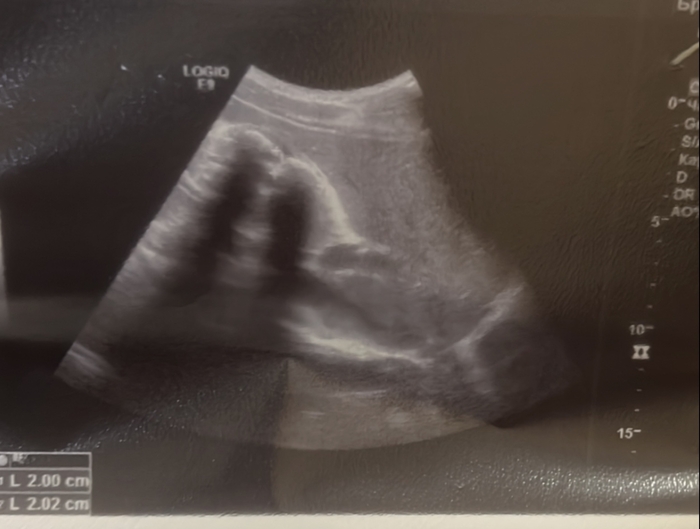

Оказывается в моём желчном пузыре, находится кладка из пары драконьих яиц, по 2 см каждое.

Операция прошла успешно и вот на свет появились они